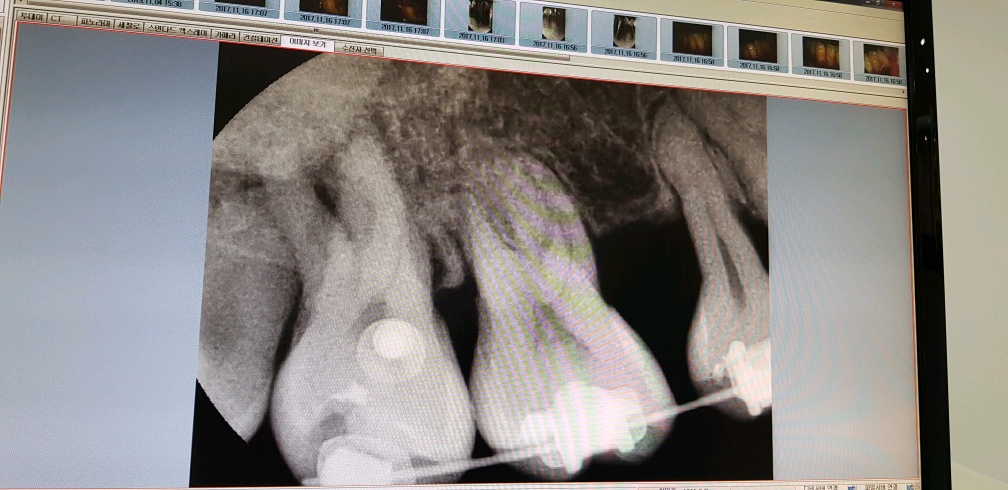

이게 확대한 부분인데 좌측에 보이는건 필요없는 사랑니라서 음식물도 끼고 하기에

제거하는게 좋다고 하더군요;;

(사실... 과거 왠쪽 어금니 뿌리쪽에 박혀있던 사랑니 제거 하다가 죽다 살아났던 기억이 있다는;;)